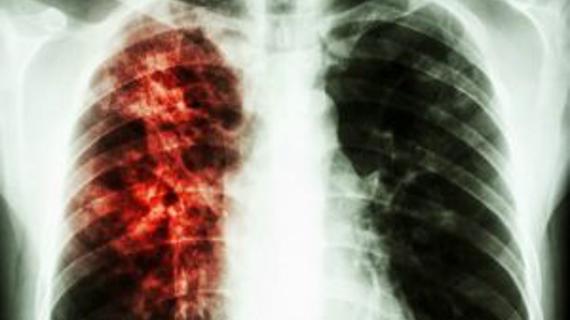

Туберкулез – это инфекционный процесс, который не теряет своей опасности на протяжении тысячелетней истории...

Врачи сталкиваются со сложностью выявления туберкулеза (чахотка, палочка Коха) у ВИЧ-положительных пациентов: из-за ослабленного иммунитета и изменения патогенеза болезни стандартные методы...